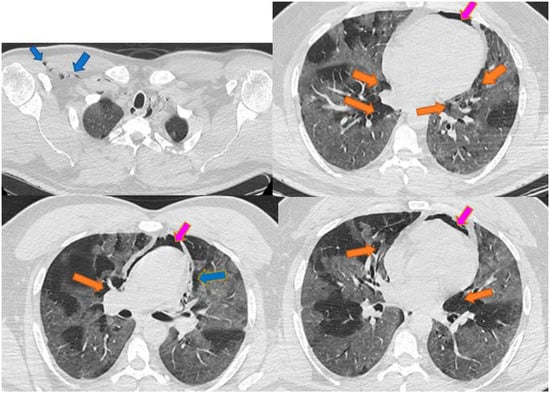

Spontaneous Pneumomediastinum, Pneumothorax, Pneumopericardium and Subcutaneous Emphysema—Not So Uncommon Complications in Patients with COVID-19 Pulmonary Infection—A Series of Cases

3. Results